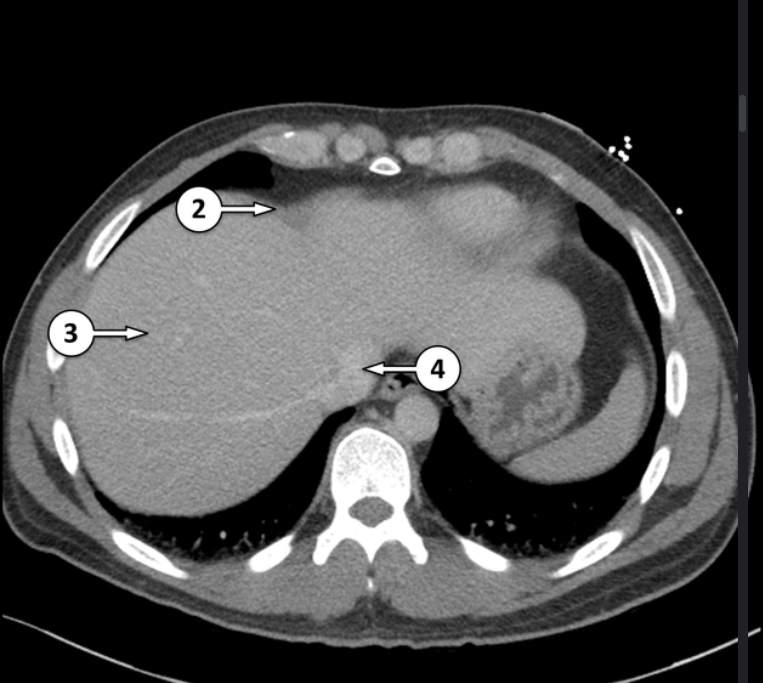

Label the CT abdomen

right hemidiaphragm

segment VIII of the liver

inferior vena cava